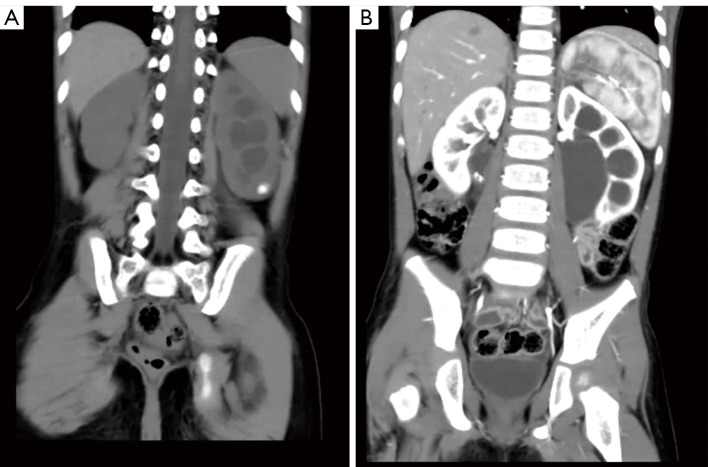

Methods: We conducted a retrospective study of pediatric patients with UPJO and renal calculi treated between March 2018 and June 2023. All patients underwent either RALP or conventional LP combined with flexible ureteroscopy. Preoperative imaging and standardized postoperative follow-up were used to assess surgical outcomes.